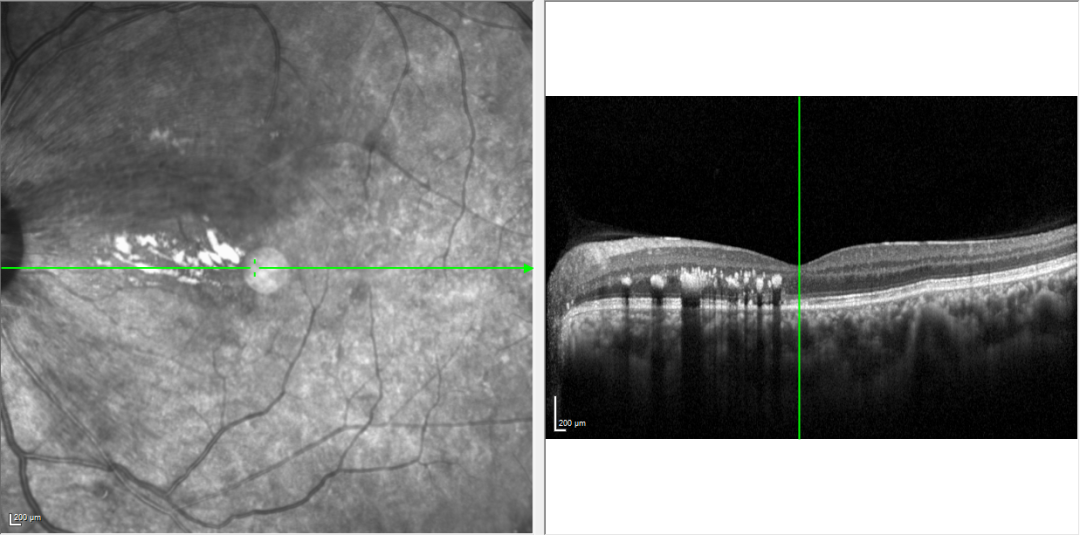

一个月后,患者再次来到我院眼科复诊。目前患者不仅血压控制良好,眼底出血也基本吸收,视力明显提高,雾视感基本消失。

提示:眼底出血基本吸收,视网膜下积液基本吸收,病情明显好转